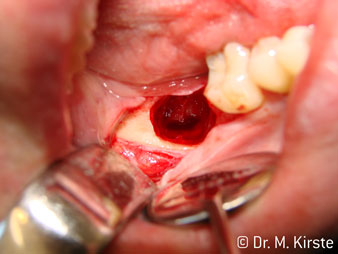

Elegir el ángulo de 45º ofrece múltiples ventajas de uso. Los odontólogos dedicados a cirugía (para quienes se desarrolló principalmente esta pieza de mano) se percatarán de inmediato de que se puede trabajar de forma muy específica. En especial en la remoción de las muelas del juicio (Fig. 2), no es necesaria una gran abducción de las partes blandas en la zona del carrillo (Fig. 3). El diseño del cabezal de la pieza de mano, combinado con los suaves giros del cabezal durante la preparación, permite trabajar de forma rápida y segura en la zona retromolar.

El nuevo diseño de los rodamientos dentro del cabezal de la pieza de mano garantiza el funcionamiento silencioso de la fresa, en la separación del diente o la raíz (Fig. 4-9) se muestra una impresionante imagen de corte sin efectos de impacto.